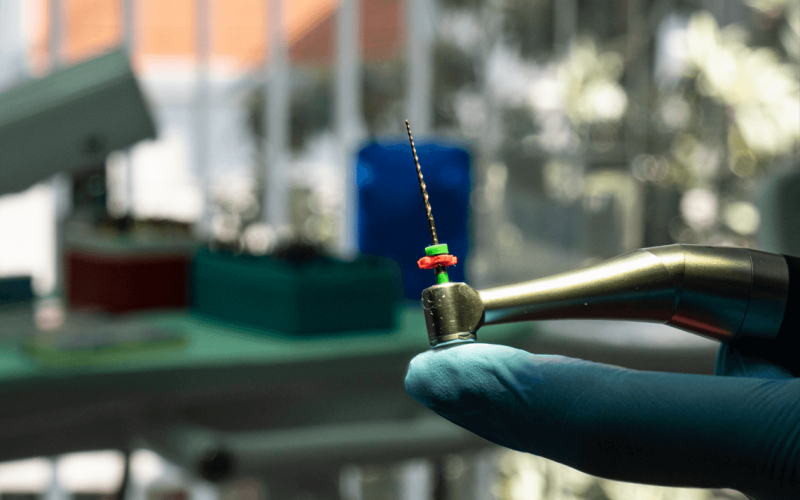

Root canal treatment, cracks and fractures in the teeth, deep decays in the teeth, cleaning, disinfecting and filling the infected tissue in the canals of the tooth with root canal filling materials as a result of the loss of vitality of the nerves and veins in the tooth is called canal treatment.